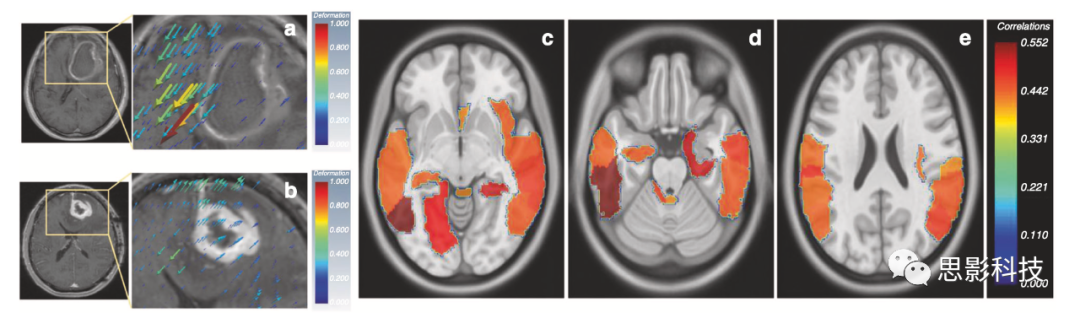

Prasanna等人討論了多序列MRI上膠質(zhì)母細(xì)胞瘤的質(zhì)量效應(yīng)誘導(dǎo)變形異質(zhì)性(MEDH)如何影響生存率。MEDH在語(yǔ)言理解、社會(huì)認(rèn)知、視覺感知、情緒、體感、認(rèn)知和運(yùn)動(dòng)控制功能等領(lǐng)域的高表達(dá)被發(fā)現(xiàn)與較差的生存率相關(guān)(圖3)。McGarry等人能夠使用新診斷的膠質(zhì)母細(xì)胞瘤的多序列MRI影像圖譜(RPs),以進(jìn)一步分層患者預(yù)后。每個(gè)檢查的體素都分配了一個(gè)RP。五個(gè)這樣的RP可以預(yù)測(cè)治療開始前的總體生存率。

3,形變影像組學(xué)

a、 b代表組織位移的變形向量顯示為疊加在右半球GBM圖像切片上的體積渲染3D抖動(dòng)。變形量與抖動(dòng)體積的大小成正比。變形量的較大值分別用“紅色”表示,較小值用“藍(lán)色”表示。震顫還顯示組織移位的方向。

c 右半球腫瘤組的AAL區(qū)域,MEDH與生存率呈負(fù)相關(guān),P<0.05(神經(jīng)系統(tǒng)視圖)。顏色貼圖顯示負(fù)相關(guān)值(顯示為正以便于表示)。